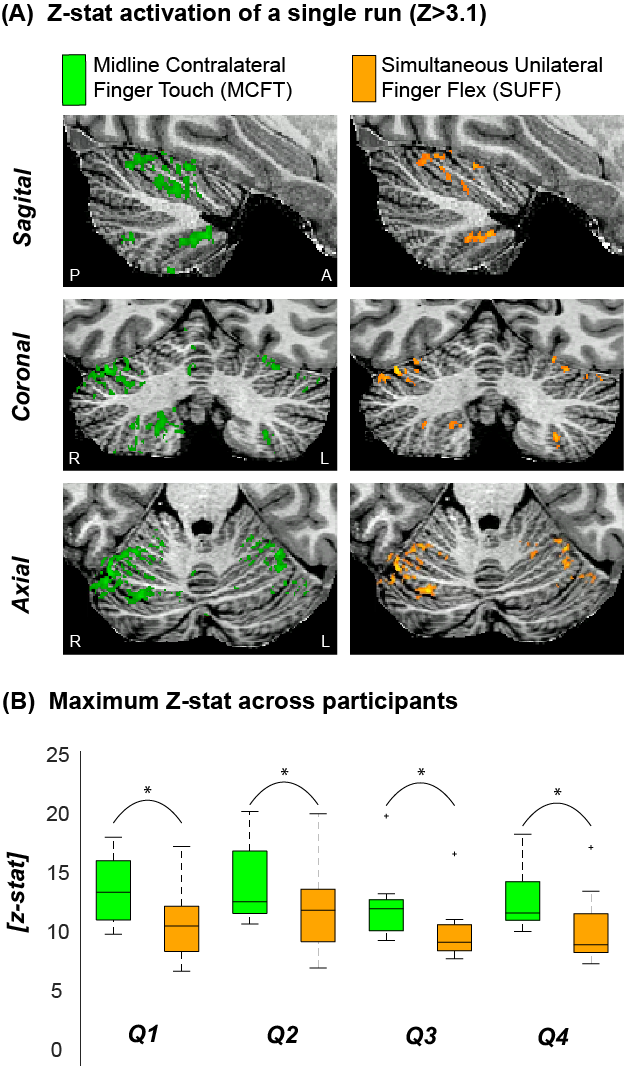

Both tasks resulted in significant activation for all participants in all four quadrants. MCFT resulted in significantly higher maximum Z-stats than SUFF across participants (P<0.05, paired t-test, Fig-2).

Figure 2: Example activation maps and maximum Z scores (A) The z-stat activation (Z>3.1) of a single run for MCFT and SUFF presented in three orientations (Sagittal, Coronal and Axial) (B) The maximum z-score for each task across participants. Note that the MCFT task resulted in significantly (paired t-test P<0.05) higher max z-stats compared to the SUFF task in all quadrants. Q1=upper right quadrant Q2=Upper left quadrant Q3=Bottom right quadrant Q4=Bottom left quadrant